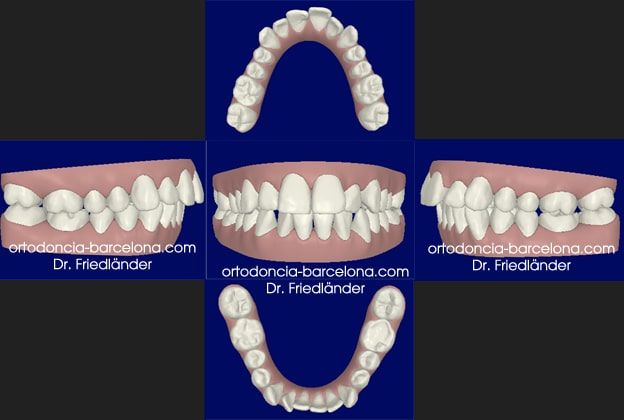

Todos los casos de Invisalign se planifican en 3D con el programa de invisalign; Clincheck; con el cual planificamos todos los aspectos del tratamiento. Antes de aceptar el plan del tratamiento se lo enseñamos la paciente y él es quien lo acepta.

Simulación del Clincheck,

Podemos ver que el final del tratamiento en boca coincide perfectamente con la planificación del Clincheck final

Simulación del Clincheck final